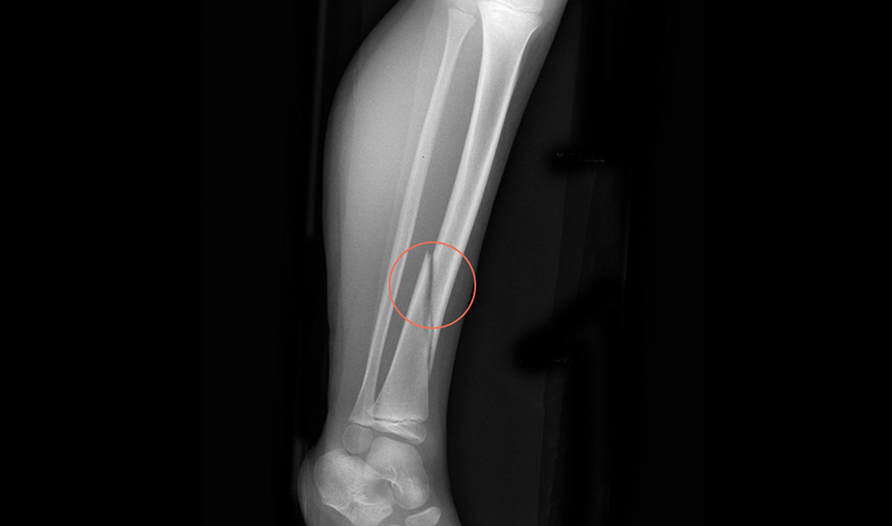

Rbfracture™

AI-powered, automatic detection of trauma-related findings

Hip fractures are the most common disabling injury and cause of accidental death in older people.

Hip fractures have a 1-year mortality rate of 22% for women and 33% for men

It is estimated that between 2-9% of hip fracture cases are missed